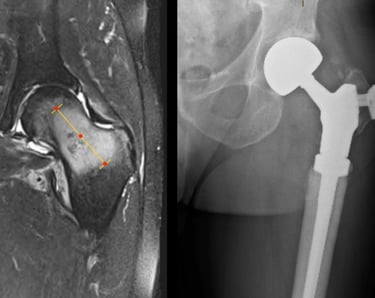

Management of these tumours can be very complex and Mr Pang is one of a few surgeons in Melbourne who has extensive experience in the surgical management of bone and soft tissue tumours / sarcomas. Management often include collaboration with other specialists of with similar interests (plastics, spinal and thoracic surgeons), complex resections such as the pelvis, utilisation of tumour / megaprosthesis and employing advanced computer navigation techniques to achieve precision tumour surgery.